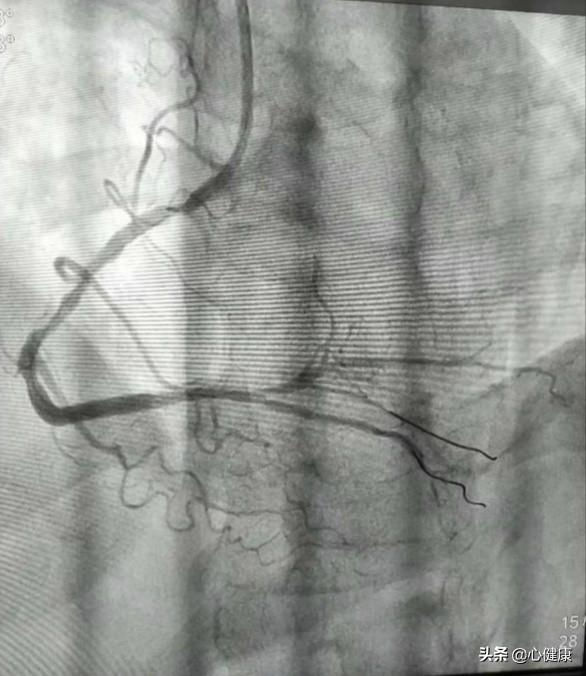

冠動脈造影とは、簡単に言えば、心臓カテーテルを用いて体の表在動脈を経皮的に穿刺することである。多くの場合、橈骨動脈または大腿動脈から穿刺し、動脈に沿って逆行性に上昇し、左冠動脈ポータルまたは右冠動脈ポータルに入り、そこで冠動脈を描出するために造影剤を注入する。

以上のようにして、左冠動脈または右冠動脈の主動脈とその分枝の内腔を明瞭に可視化し、冠動脈系の血管に狭窄病巣が存在するかどうか、また狭窄の程度を確認することができる。その後、治療計画を決定することができる。例えば、外科的バイパス術を行うか、保存的内科的治療を行うか。あるいは全く治療を行わないこともある。

(2)具体的な手順:患者は心臓カテーテル検査室の手術用ベッドに横たわり、手術部位を消毒し(手または大腿部)、この部位に局所麻酔薬を投与し、動脈血管に針で穴を開け、細いガイドワイヤーとカテーテルを送り、X線の監視下で血管をたどって冠動脈までガイドワイヤーカテーテルを到達させ、細いカテーテルの頭部に一種の薬(造影剤)を注入することで、X線の下に血管が映し出され、血管の大きさ、進み方、閉塞の有無、左冠動脈、右冠動脈、各枝などが一目でわかる。X線の下に血管が映し出され、血管の大きさ、進み方、詰まりの有無、左右の冠動脈、各枝などが一目でわかる。問題が深刻でなければこれで終わりで、カテーテルを抜き、出血を防ぐために手首の穿刺部をコンプレッサーで圧迫する。熟練していれば、全行程で10~30分かかる。問題が深刻な場合は、治療(バルーン拡張術、ステント留置術など)が続き、時間がかかることがあります。

現在。95%以上の患者が手首の橈骨動脈から行っている。医師は、橈骨動脈から冠動脈の開口部にホースを挿入して心臓の冠動脈の開口部に送り、造影剤を開いてX線を照射することで、心臓の血管が鮮明に見えるようにし、医師はその画像の展開を観察することで、心臓の動脈が狭窄しているかどうか、詰まっているかどうか、詰まっている場合はどの程度詰まっているのかを判断することができる。そこから冠動脈疾患なのか、他の心臓病なのかを判断することができる!

冠動脈造影と心臓(心房と心室)造影がある。 冠動脈造影検査は、橈骨動脈(手首のところ)または大腿動脈(太もものところ)に沿って毛細血管の細いカテーテルを使い、心臓の冠動脈の開口部に人工的な入り口を拡張し、冠動脈内に造影剤(X線内)を注入することで、冠動脈の内部形態を示すことができ、例えば、冠動脈の狭窄がないか、プラークがないかなどを見ることができますが、基本的には心臓の形態を検査することによって理解することはできませんが、冠動脈の内部形態と冠動脈内の血流速度、心臓を理解することが主眼となります。冠動脈の内部形態と冠動脈内の血流速度を理解することが主な目的である。